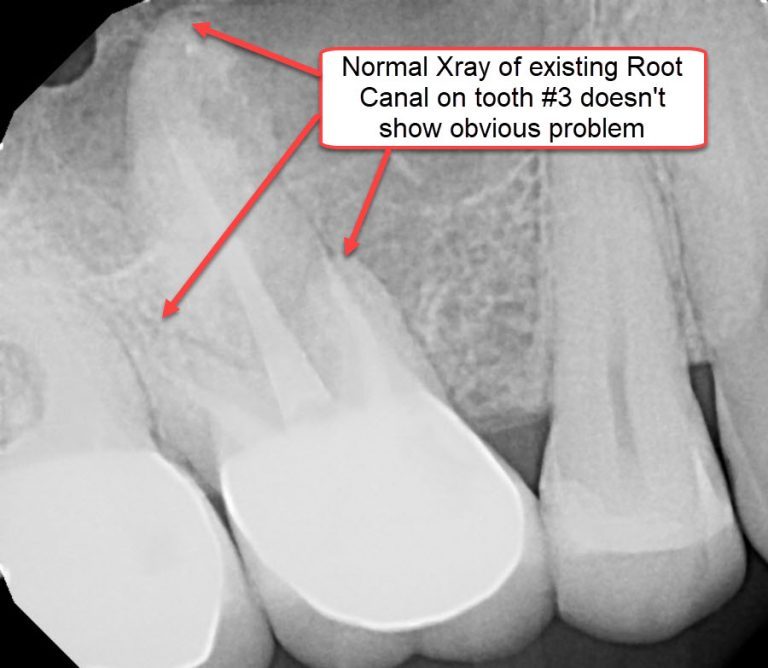

Infected Root Canal XRay What is it and how much does it cost? What Is Root Canal Infection Root canal treatment is not painful and. Root canal treatment (endodontics) is a dental procedure used to treat infection at the centre of a tooth. An injury, such as a blow to your mouth. This infection can cause severe discomfort and, if left. A tooth root infection, if left untreated, can cause irreparable damage to the tooth and even spread. What Is Root Canal Infection.